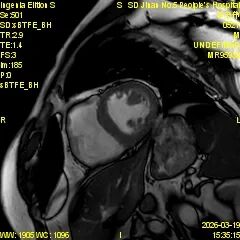

为进一步提升心血管疾病精准诊断水平,满足临床诊疗和患者就医需求,济南市第五人民医院影像科精心筹备、多措并举,顺利开展心脏磁共振(CMR)新技术,目前已完成心脏磁共振检查近30例,取得了良好效果,标志着医院心血管影像诊断能力迈上新台阶。

心脏磁共振被誉为评估心脏结构、功能及心肌组织特征的 “金标准”,具有无创、无辐射、多参数、精准度高等优势,可以为心肌病、冠心病、瓣膜病、先天性心脏病等疾病提供全面、客观的影像学依据,对临床制定治疗方案、评估预后具有重要意义。